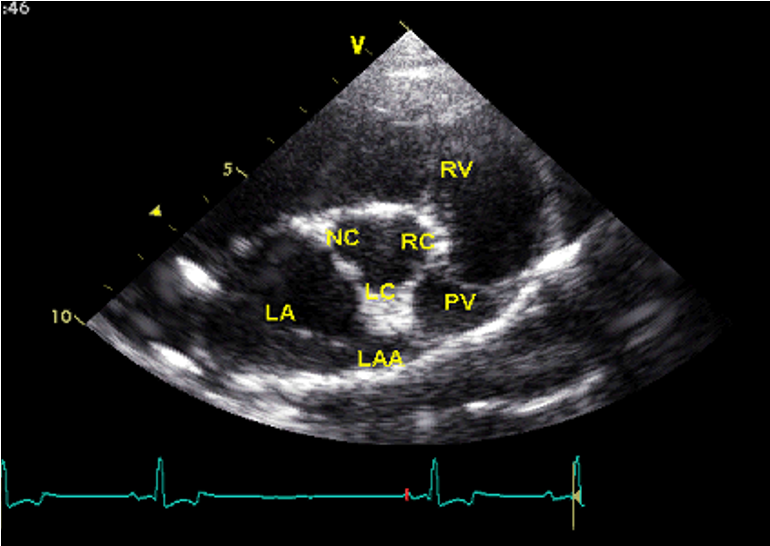

Which view is this?

A

Right parasternal short axis @ aortic valve